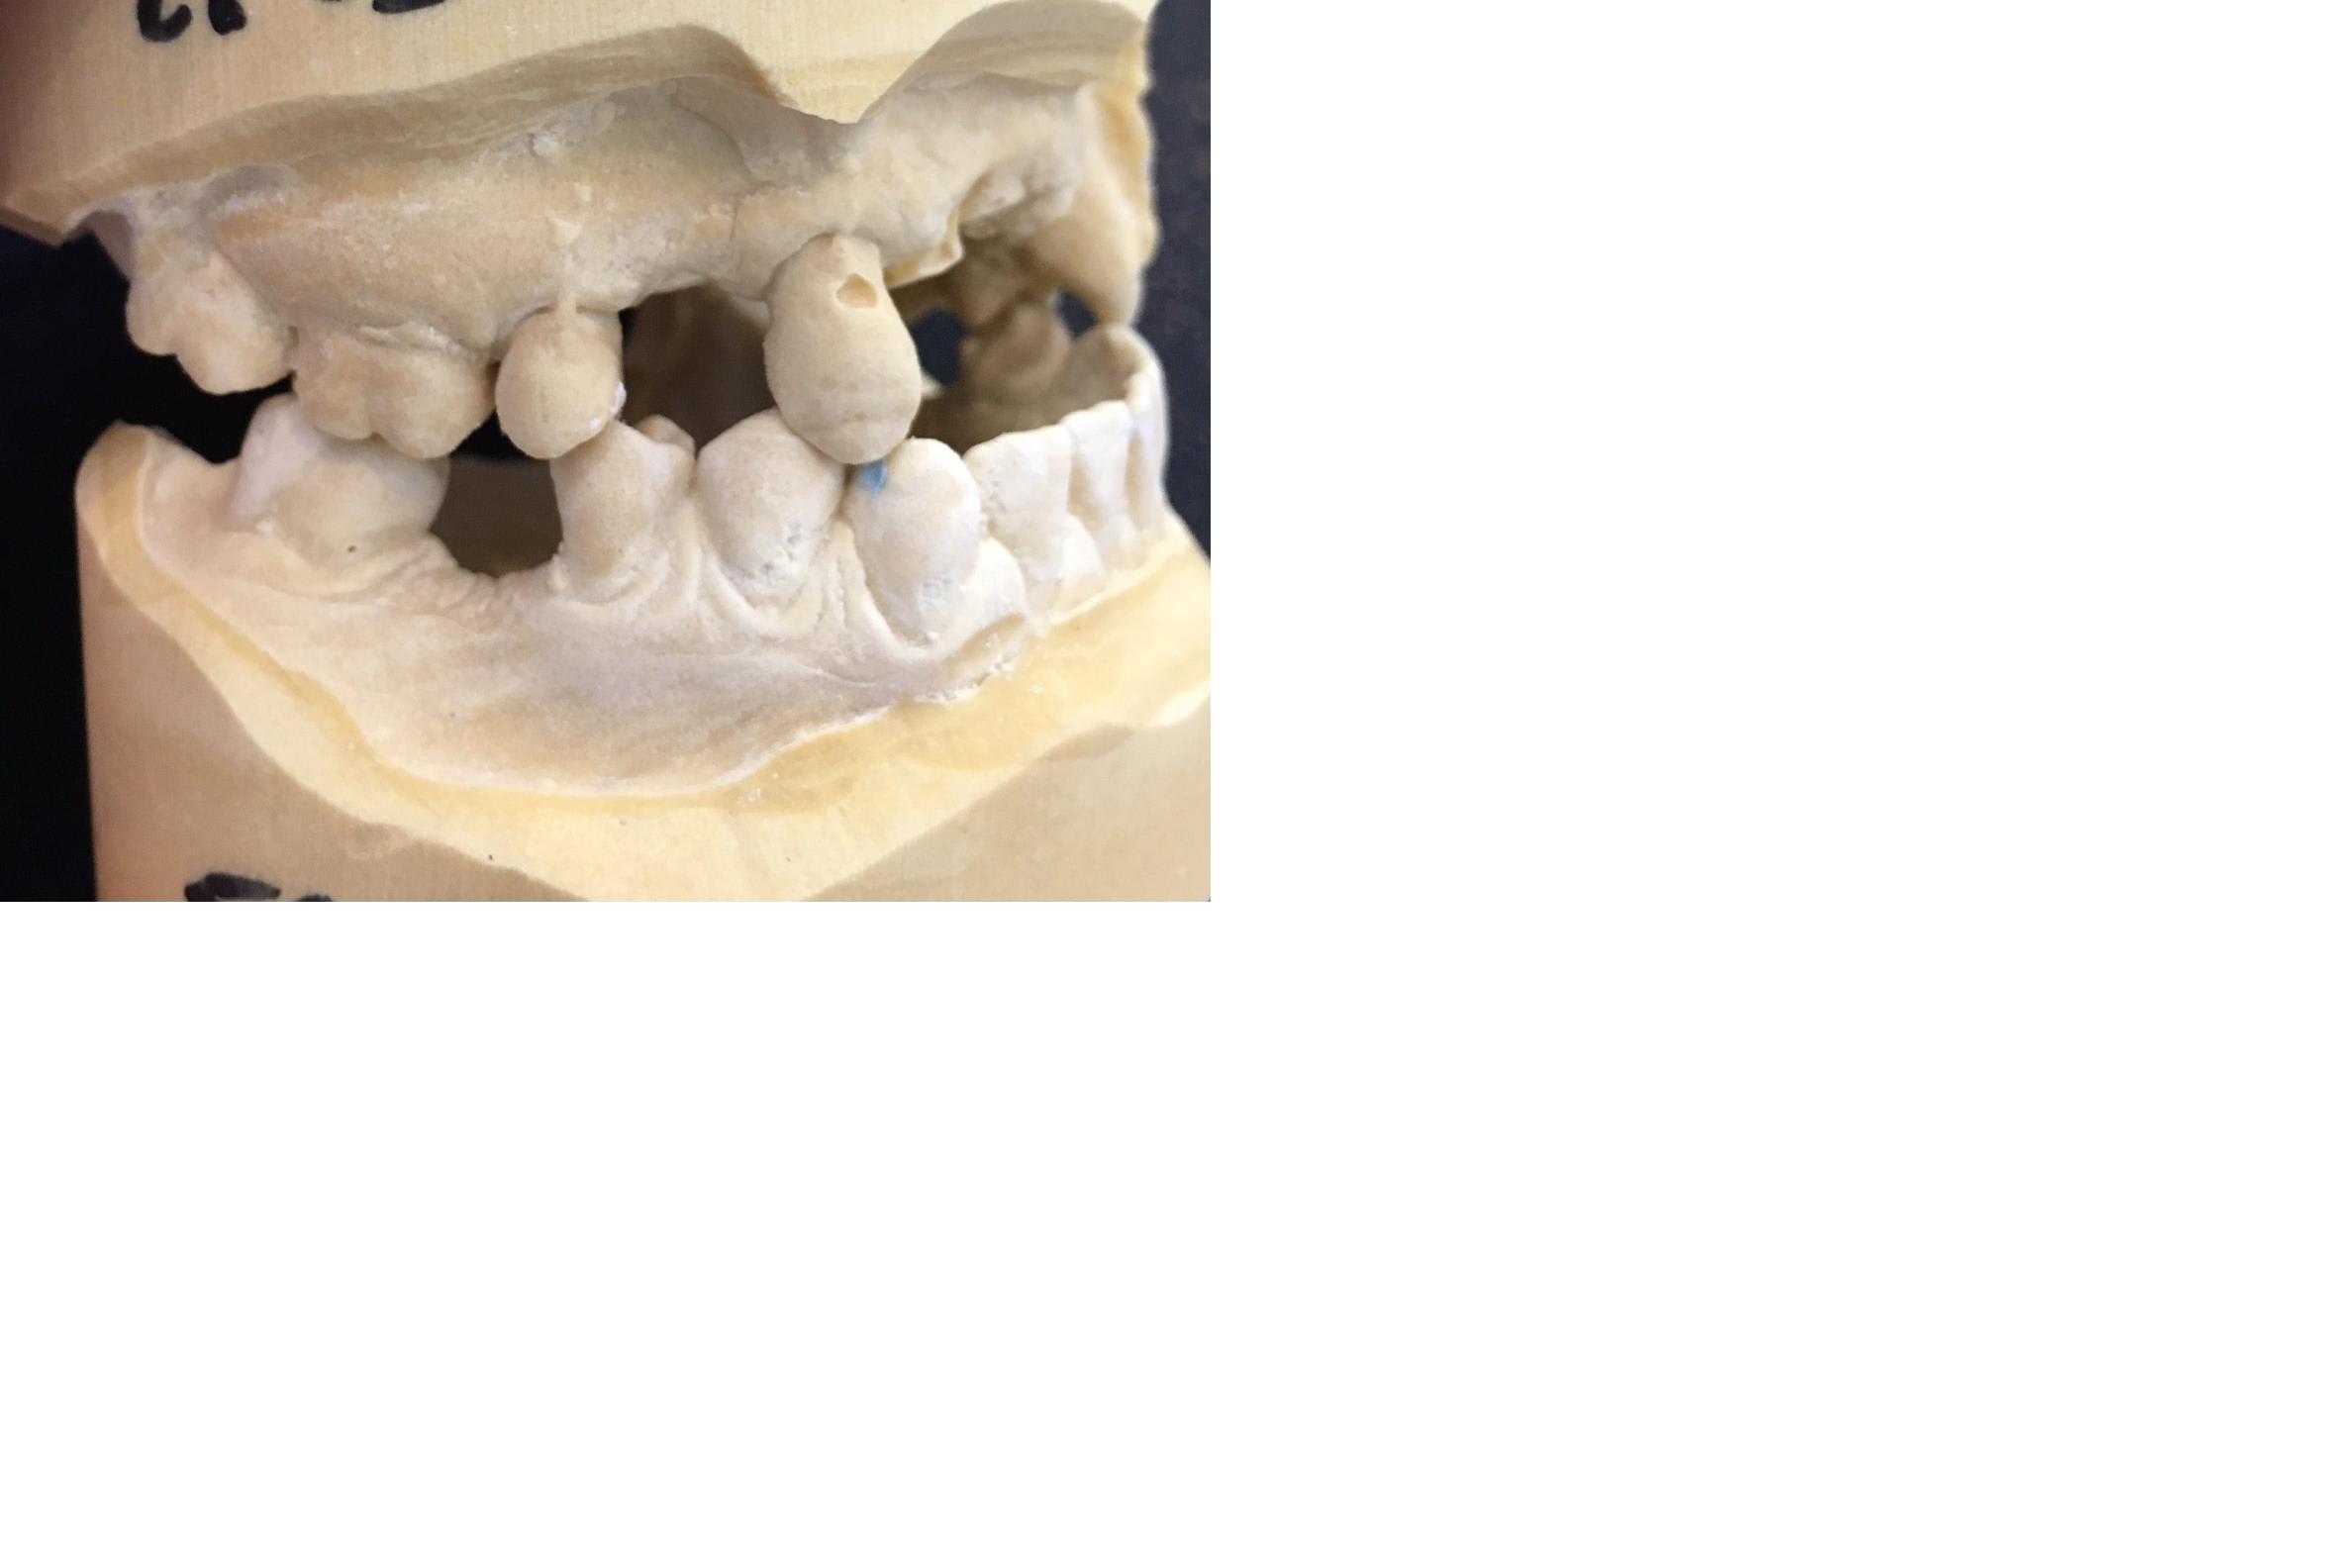

Je reçois une nouvelle patiente :

Pas de soucis de santé mais fumeuse 20 cigarettes par jour

Elle a subi de nombreux échecs implantaires :

- nécrose d'une greffe ramique au niveau de 21/22

- implants déposés puis reposés

Elle découvre très peu même lors d'un sourire forcé.

J'aimerais avoir vos avis.

Je lui proposerais pour remplacer ses incisives maxillaires :

- sans arrêt du tabac : un stellite pour remplacer ses incisives maxillaires

avec dépose de l'implant en 11 et réenfouissement de l'implant en 12

- avec arrêt du tabac : réaliser un bridge provisoire 13-12-(11/21/22)-23-24 MAIS en mutilant 3 de ses dents (13,23 et 24) mais pour m'assurer d'avoir une prothèse fixe qui me permettra de greffer le secteur 21/22